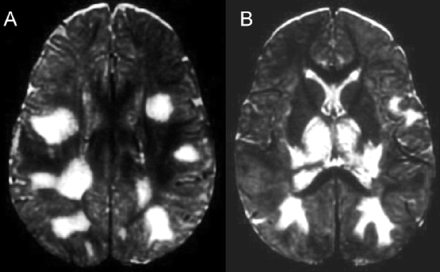

提出了四种模式的大脑参与描述ADEM的磁共振成像结果21:1)ADEM小病变(少于5毫米;图1);2)ADEM大支流,块状病变,簇状或频繁广泛perilesional水肿和质量效应(图2);3)ADEM附加对称bithalamic参与(图3);和4)急性出血性脑脊髓炎(咳咳),当一些出血的证据可以确定大脱髓鞘病变(图4)。核磁共振成像模式似乎并不与任何特定的结果或残疾,作为大型儿童群体中观察到,21因为大多数病变往往解决后续成像研究。21日,32然而,这种分类可能是有用的在考虑的鉴别诊断ADEM和可能有助于识别那些孩子来说,初始ADEM-phenotype真的是第一个女士的表现。

图4。急性出血性脑脊髓炎。(A)轴向t2加权MRI与著名的双边hyperintense病变区域的信号很低,相应的血红蛋白的分解产物,在一个5个月大的孩子男孩,百日咳疫苗接种后2周。(B)轴向t1加权磁共振成像相同的情况下,显示自发hyperintense大hypointense内病变的信号。